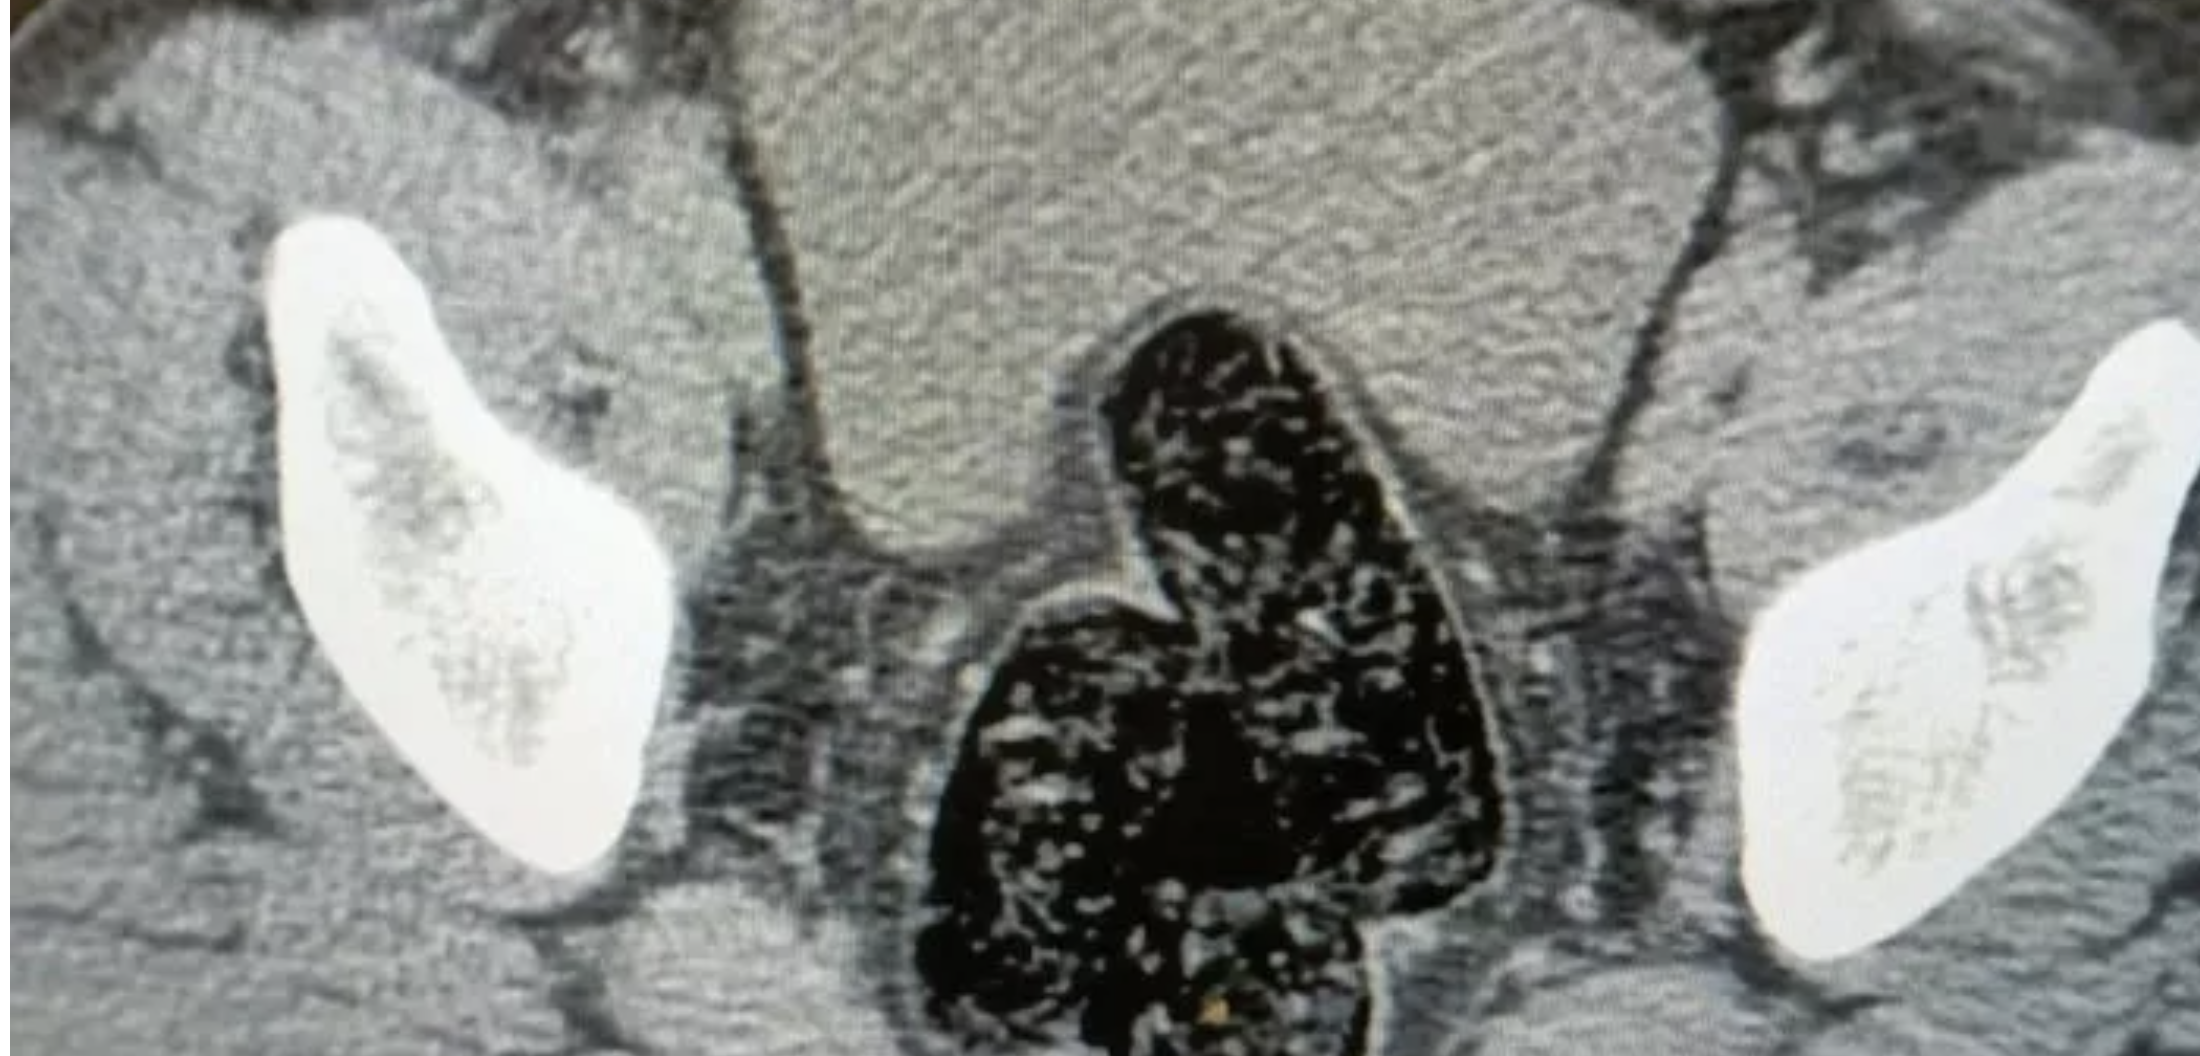

Şahsın devam eden işlemlerinde gözlerindeki kızarıklık, yemek ihtiyacı istememesi, aşırı tedirgin davranışlar sergilemesi üzerine yapılan iç beden muayenesi neticesinde röntgen vasıtasıyla makat ve bağırsak kısmında uyuşturucu kapsülleri olduğu tespit edildi. Doğal yöntemlerle şahıstan 12 adet kapsül toplam daralı ağırlığı 345.19 gram gelen metamfetamin ele geçirildi. Şahsın üzerinden ve iç bedeninden toplamda 355.36 gram uyuşturucu madde ele geçirildi.